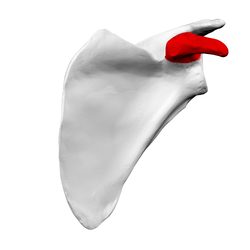

Left scapula. Anterior view. Coracoid process shown in red. | |

Anterior view. Coracoid process shown in red. | |

Left scapula. Coracoid process shown in red.

Left scapula. Coracoid process shown in red. Animation. Coracoid process shown in red.